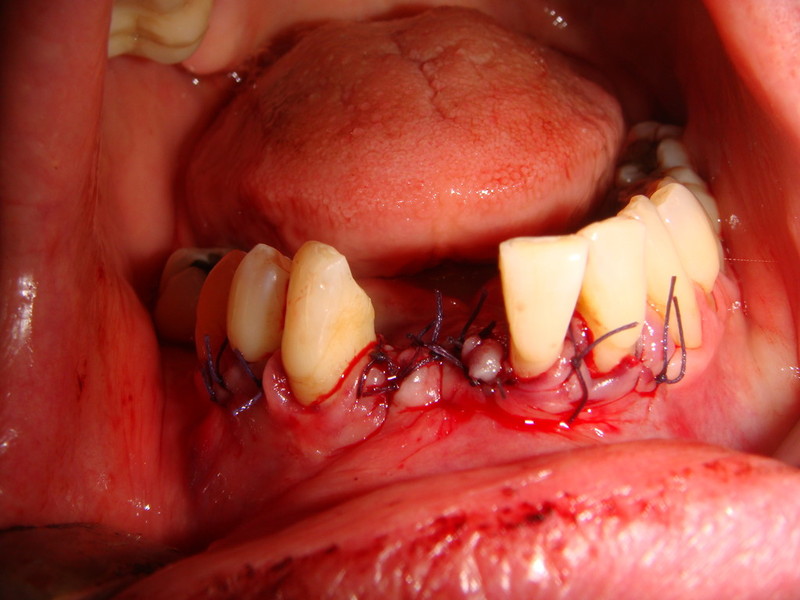

Rigenerazione Gravi difetti parodontali

rigenerazione grave difetto parodontale a carico una intera emiarcata